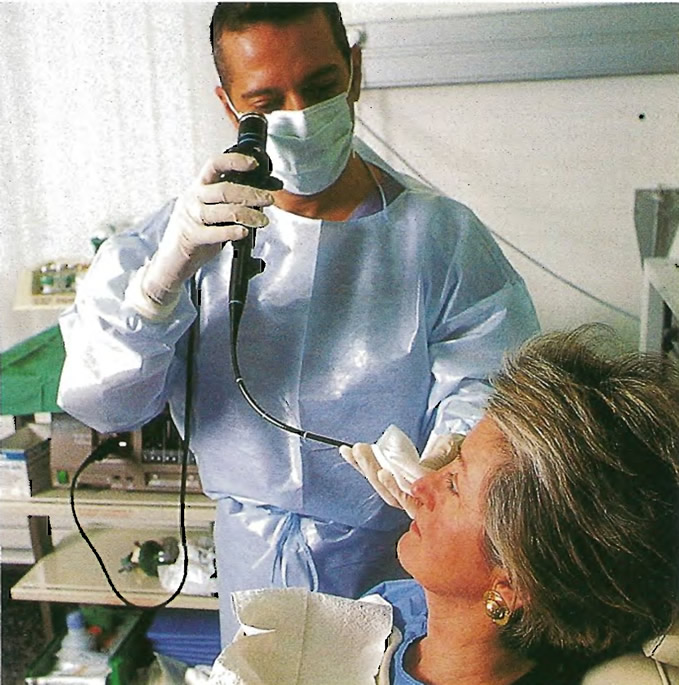

Фотографии и информация о бронхоскопии при туберкулезе